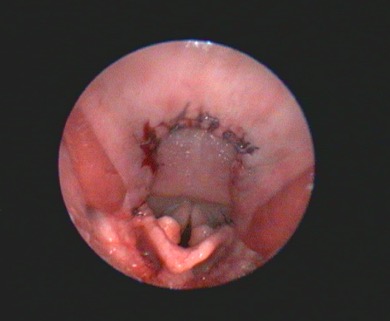

Additional diagnostic tests that can give information beyond the direct preoperative visual observation of the nostrils, soft palate (Figure 1), tonsils, laryngeal saccules (Figure 2) and laryngeal cartilages can include thoracic radiographs, computed tomography (CT) and pharyngoscopy/rhinoscopy. Findings can include aberrant nasal turbinates, aspiration pneumonia, hiatal hernia (and other oesophageal conditions), nasopharyngeal mucocoele and tracheal/bronchial disease.